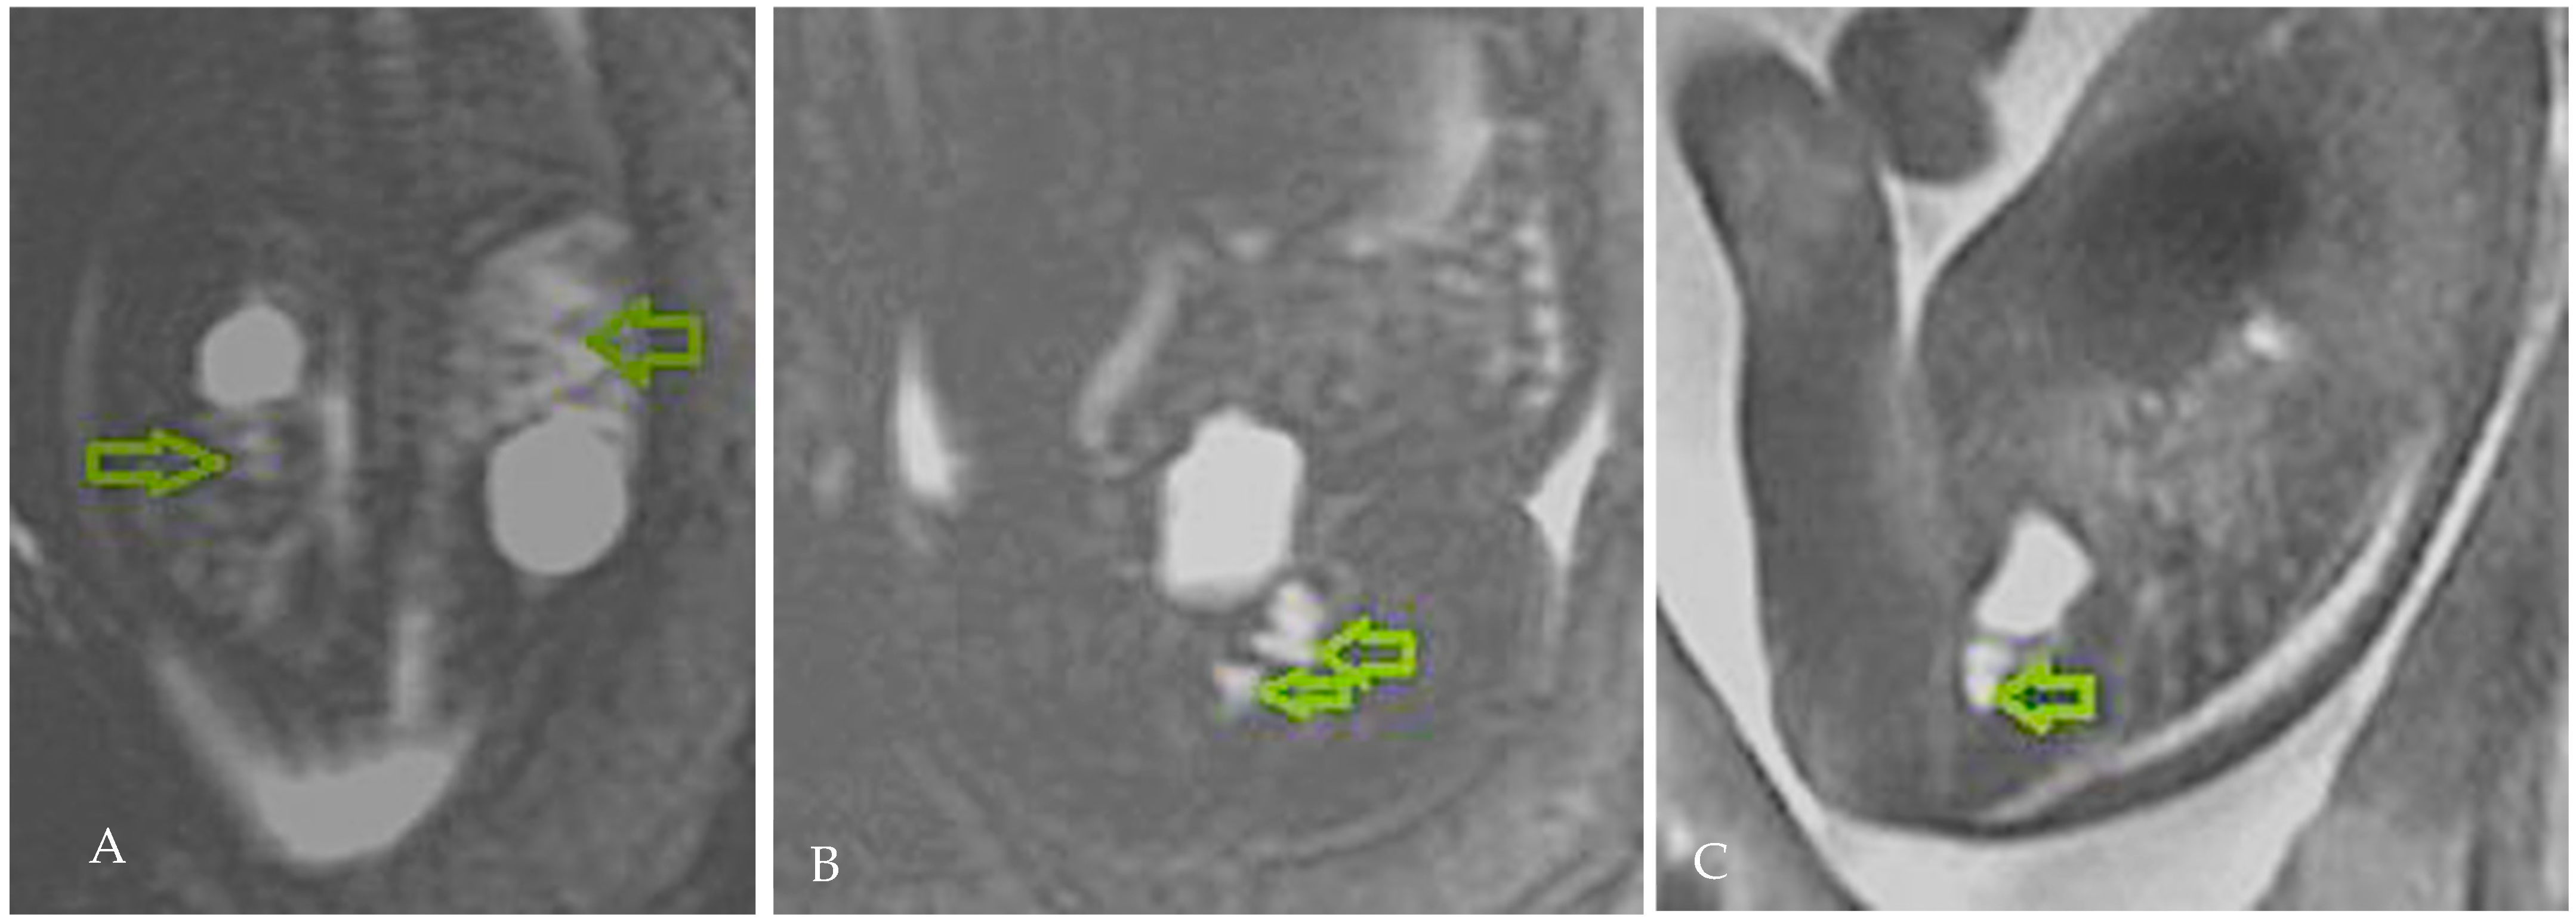

2. Case Presentation